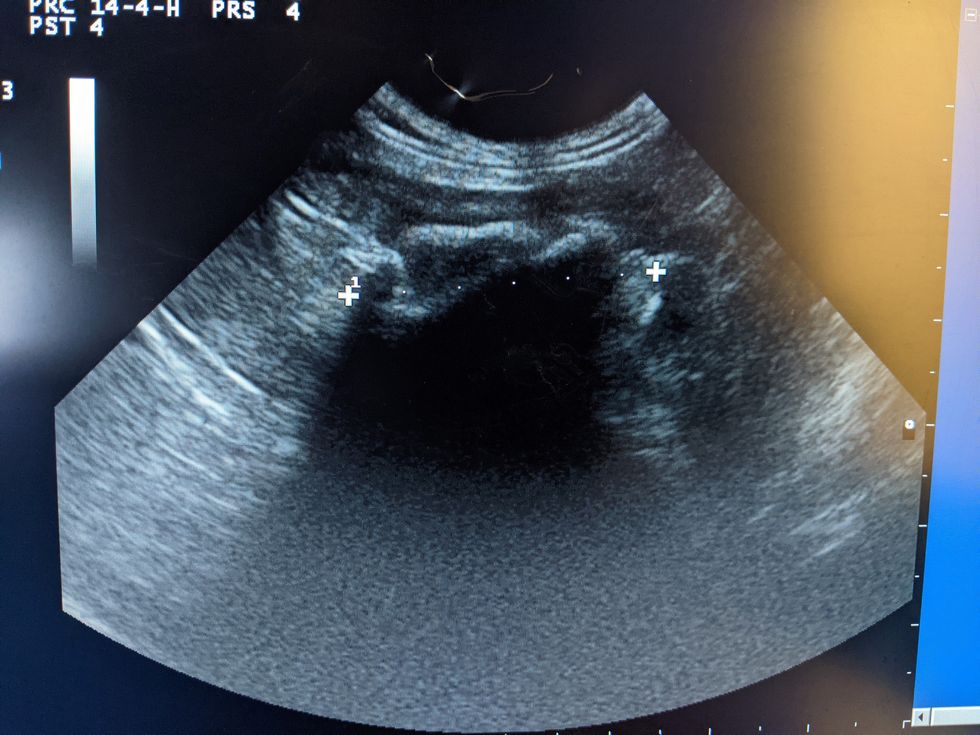

Blue Cross staff told her to take Toffee into their animal hospital in Victoria immediately, where he was put on a drip. An ultrasound scan confirmed a large object stuck in his stomach.